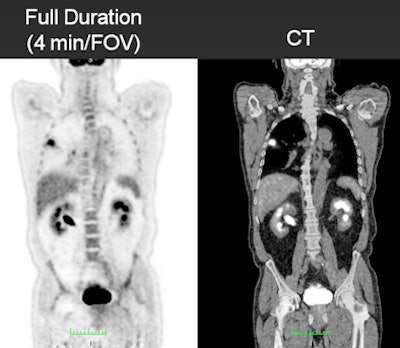

In the study, 20 patients with a mean weight of 165 lb (range, 105-297) received whole-body PET/CT scans (Gemini TF, Philips Healthcare) one hour after injection of 10 mCi of the radiopharmaceutical. Fixed image acquisition durations were set at four minutes, two minutes, and one minute per field-of-view (FOV).

Two reviewers evaluated 115 lesion sites to determine PET/CT's accuracy, with the full duration of four minutes used as the reference standard. Maximum standardized uptake values (SUVs) of primary lesions and noise in the liver were evaluated, along with image quality, which was rated on a scale of 1 (unacceptable) to 5 (excellent).

| The series of images shows image quality over the course of the PET/CT scan in a 178-lb patient. All images courtesy of Adam Alessio, PhD. |

Regarding image quality, the full four-minute study achieved the best image quality, which the two readers rated an average of 4.25. As image acquisition time decreased, so did image quality. Readers rated images from the two-minute duration as 3.8 and from the one-minute duration as 2.9.

"The full-duration studies were deemed to be good to excellent [image] quality; the half-duration were good to very good quality, and the quarter-duration was a little worse," Alessio said. "None of the studies -- even the quarter-duration -- were considered unacceptable. They all had information content and were within the bounds of our two readers for acceptability."